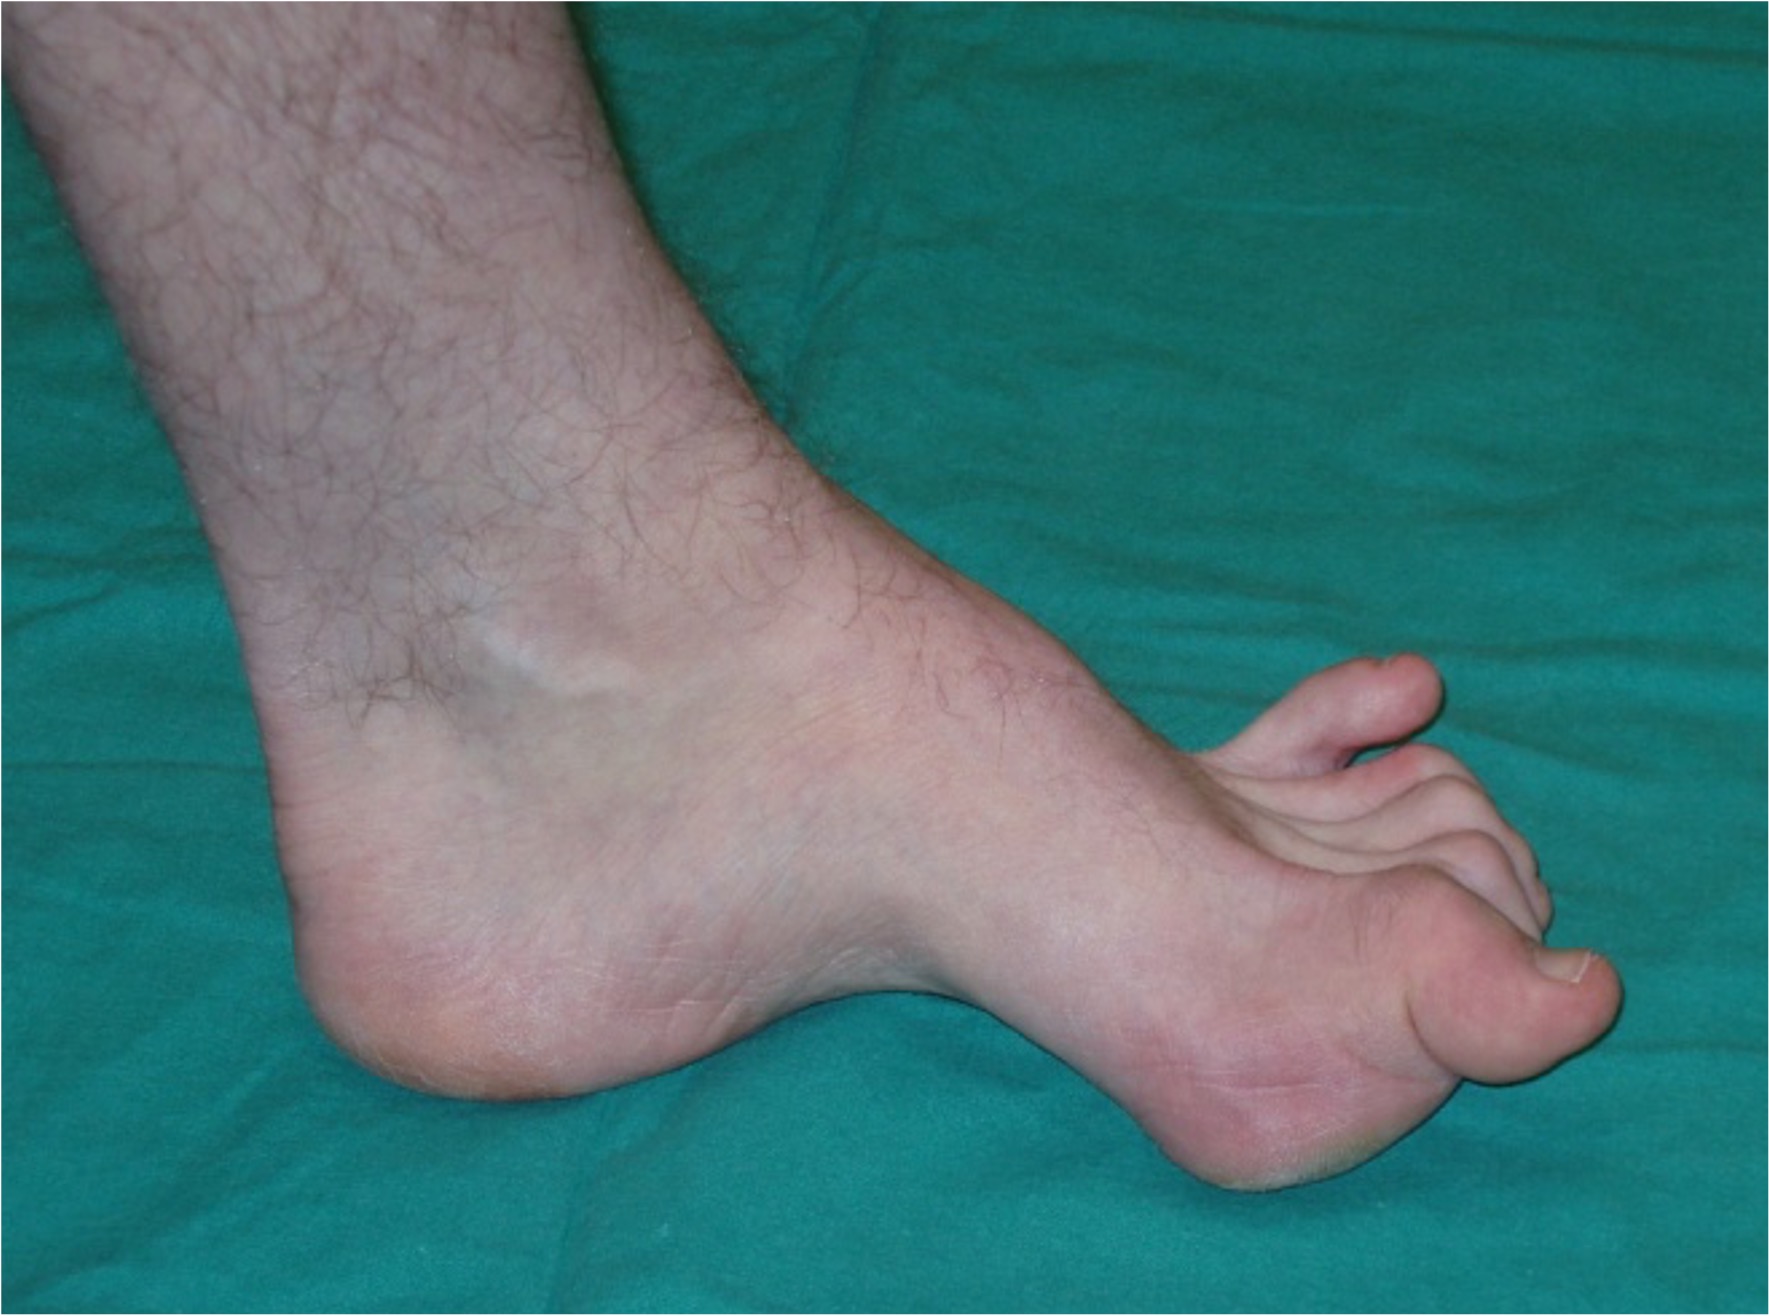

Figure 1: A cavovarus foot

- The cavovarus foot is a foot with a high arch that maintains its position on weight bearing.

- Pathology can be found in the hindfoot, midfoot, forefoot or a combination.